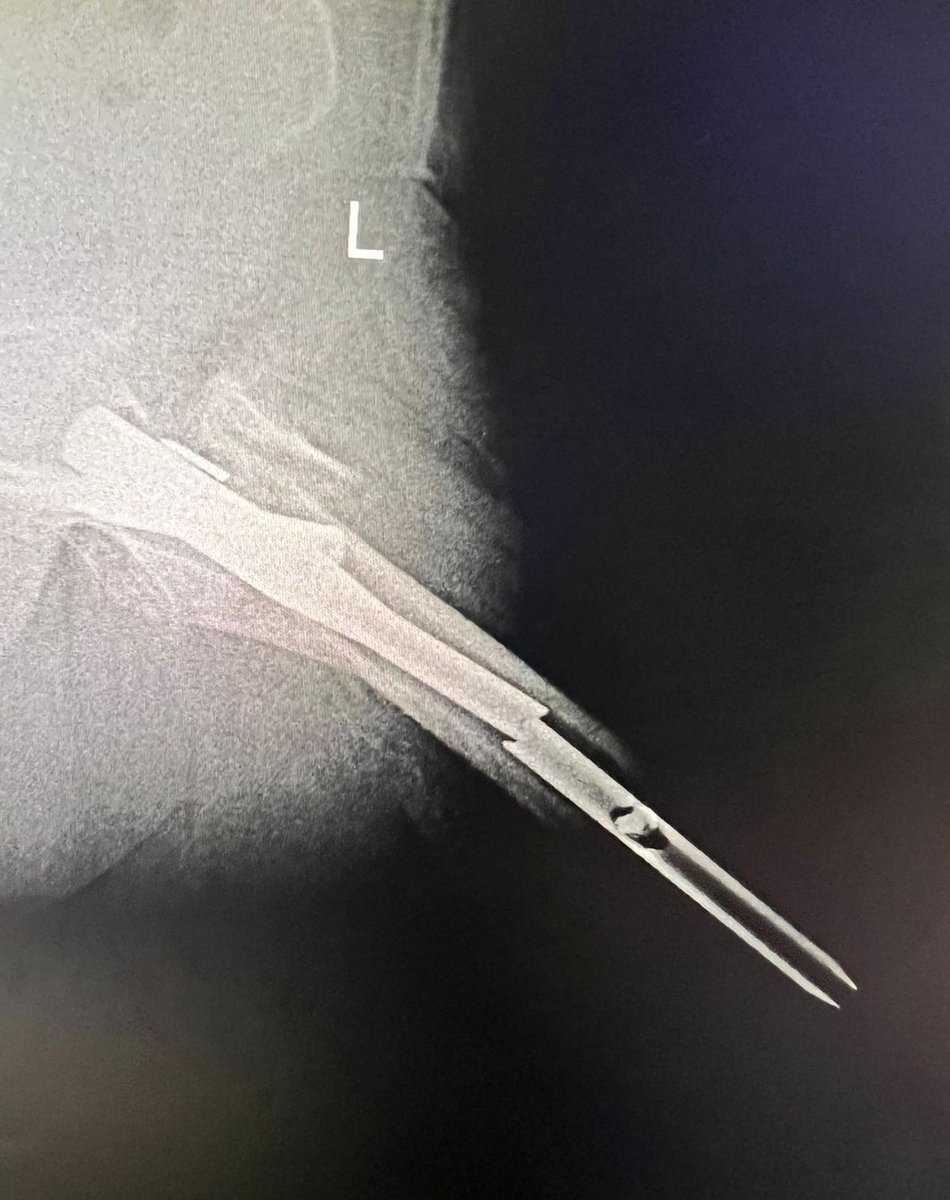

I’m bionic for real now 🦾